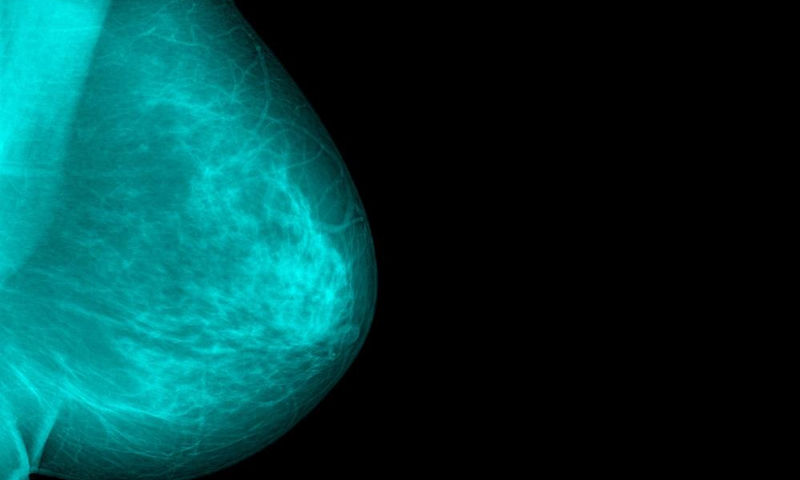

Καρκίνος του μαστού: Ο ρόλος των αποβολών

Ο κίνδυνος προσβολής από καρκίνο του μαστού μετά από μια αποβολή είναι ιδιαίτερα αυξημένος κατά τη μετεμμηνοπαυσιακή περίοδο.